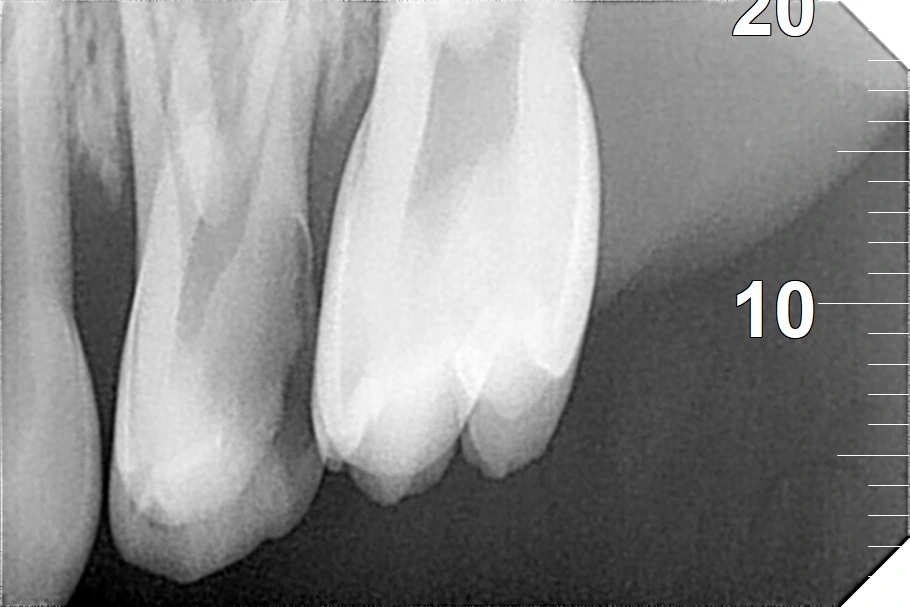

Clinical examination suggested gross caries in the primary maxillary first molar (#I), tenderness on percussion, intraoral swelling, and a sinus track. An intraoral periapical radiograph (IOPAR) revealed deep proximal caries that involved the pulp with periapical infection. The behavior rating was Frankl's Negative (--), which meant anxiety.

Biomechanical preparation was performed using 16mm pediatric rotary files under magnification, ensuring thorough cleaning. Canals were sprayed liberally with sodium hypochlorite solution. The canals were obturated using Metapex (a resorbable, calcium hydroxyapatite-based paste ideal for primary teeth).\